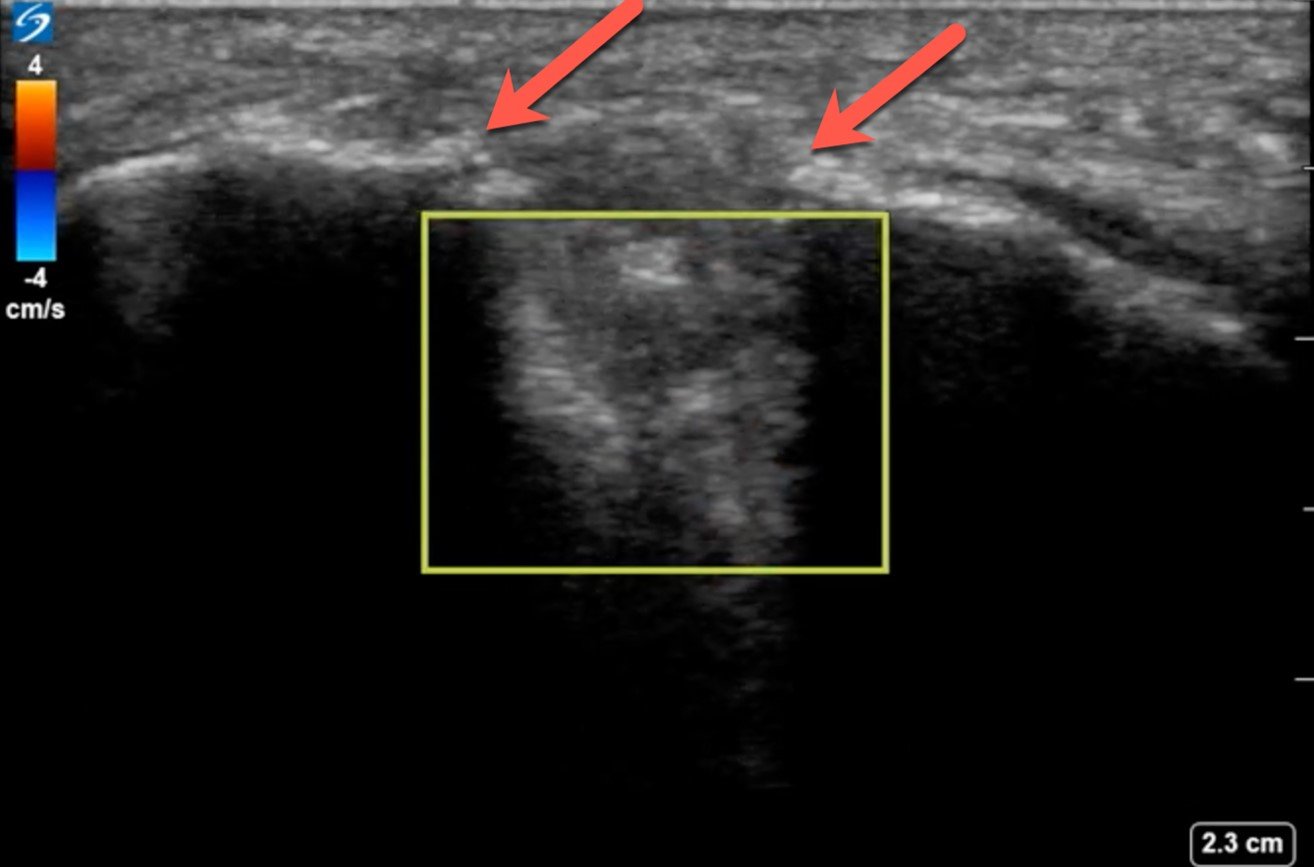

Using the high-frequency linear probe, typical views are obtained superior and inferior to the patella, as well as medial, lateral, and posterior to the knee joint. Views superior and inferior to patella assess for the integrity of the quadriceps and patellar tendons, the patella, as well as presence of knee effusion. Normal examination of the overlying skin and absence of cobblestoning of the soft tissue on ultrasound lessens the likelihood of cellulitis and abscess. Figure 1 shows the anterior ultrasound view of the knee, the patella. An intact patella should demonstrate the uninterrupted hyperechoic curvature of the cortical surface. In figure 1, we see an unmistakable cortical disruption (between the two red arrows), indicating a patellar fracture. Knee effusions will appear as an anechoic collection, indicated by the blue arrow, deep to the tendons. (Fig. 2) Medial and lateral views can also demonstrate effusions. Complex effusions such as hemarthrosis appear as hypoechoic collections if clotting has occurred. Figure 3 demonstrates a traumatic hemarthrosis identified by the green arrow. Figure 4 shows another simple knee effusion, indicated by the green arrow, without a history of trauma. Aspiration in the emergency department or office can be useful in directing therapy. In Figure 4, we see the needle approaching the effusion from the left side of the screen highlighted by the red arrow. Lastly, the posterior aspect of the knee contains the popliteal vessels. The popliteal vessels should be identified by Color Doppler, allowing differentiation from the non-vascular structures. Figure 5 shows a cystic non-compressible, anechoic structure without internal echoes within the popliteal fossa highlighted by the yellow arrow.

Figure 1